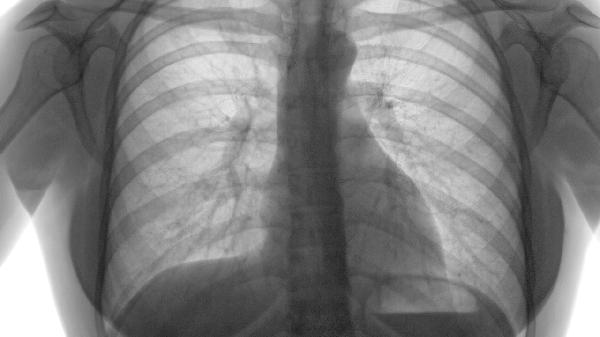

胸部X线检查是诊断肺气肿的初步筛查手段,可显示肺野透亮度增高、横膈低平、肋间隙增宽等特征性改变。早期肺气肿可能仅表现为肺纹理稀疏,随着病情进展会出现典型肺过度充气征象。该检查具有操作简便、费用较低的优势,但对轻度肺气肿的敏感性有限。